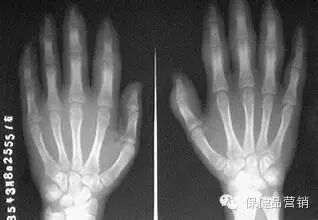

(1)、X线片关节X线片可见软组织肿胀、骨质疏松及病情进展后的关节面囊性变、侵袭性骨破坏、关节面模糊、关节间隙狭窄、关节融合及脱位。

(6)手部关节X线片改变(表现为关节及其邻近骨质疏松或明显的脱钙现象,关节间隙的狭窄)。